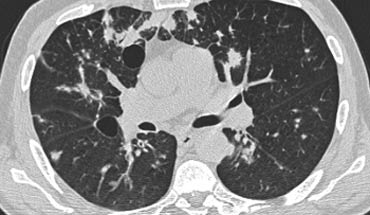

Hãy cuộn qua các hình ảnh bên trái.

Có nhiều vùng đông đặc.

Các dấu hiệu kèm theo bao gồm hạch to rốn phổi và trung thất.

Chẩn đoán phân biệt trên hình ảnh CT về cơ bản giống như trên X-quang ngực.

Kết quả mô bệnh học xác nhận sarcoidosis phế nang.

Chỉ có một gợi ý duy nhất cho chẩn đoán, đó là sự hiện diện của các nốt nhỏ có thể nhận thấy ở hình 3, nhưng rất khó quan sát.

Trường hợp này minh họa rõ ràng rằng sarcoidosis thực sự là “kẻ bắt chước vĩ đại”.